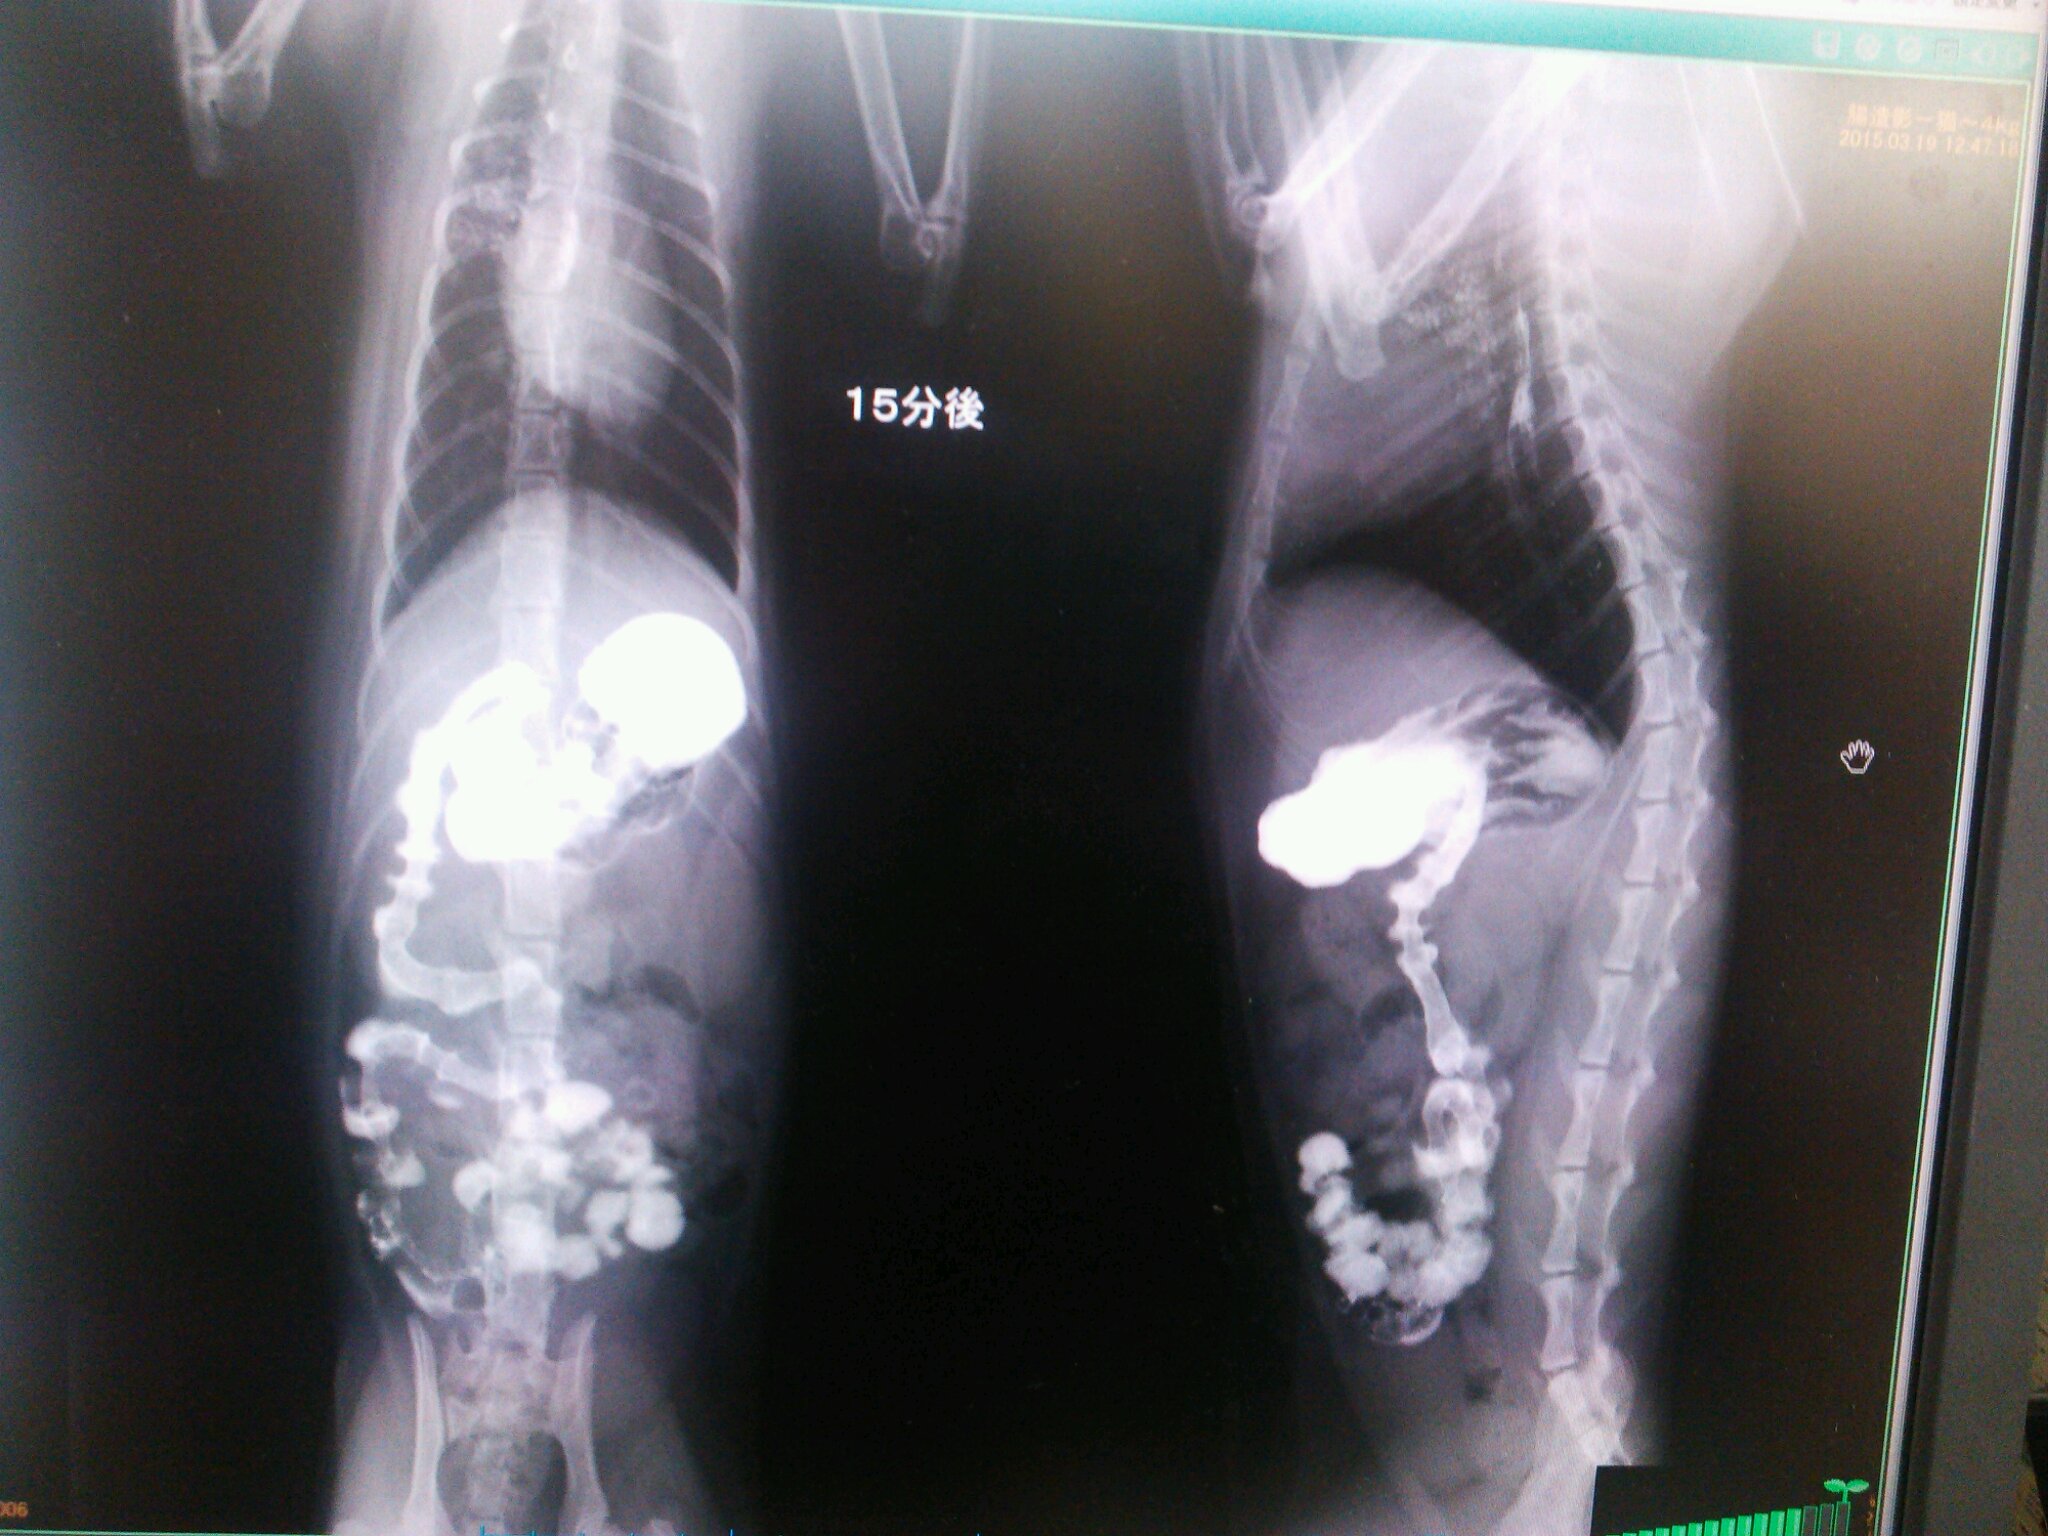

こんなカンジでバリウムが流れていって

どっかで止まれば、そこが腸閉塞っつー話でやんすた。

こんなことを5時間以上続けたらしい。